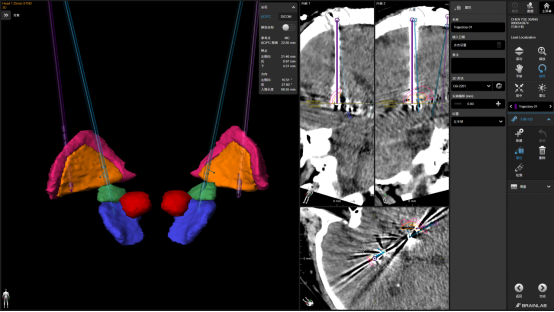

手术由谭守刚DBS功能团队联合北京301医院专家顺利完成,凭借丰富的经验和娴熟的技术,在立体定向框架与多模态影像融合技术的引导下,将电极精准植入预设核团。术后给予低电量刺激时,患者眼睑及面部的抽动现象即刻得到显著改善,这为手术团队注入了极大的信心。术后复查显示,电极位置精准,达到预期目标。术后第三周,病人经神经调控后症状改善非常满意。